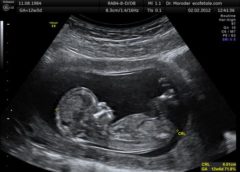

LeggiUltrasuoni per prevedere un parto pretermine

Prevenire il rischio di un parto pretermine ora sarà possibile grazie agli ultrasuoni. Come spiegano i ricercatori della facoltà di infermieristica dell’Università dell’Illinois di Chicago che hanno fatto la scoperta, gli ultrasuoni ridotti o attenuati delle ecografie sarebbero dunque un segnale rivelatore, perché consentono di rilevare i cambiamenti nell’assorbimento dell’acqua…

Un biotecnologo sta lavorando su un apparecchio ecografico portatile che potrebbe rimpiazzare i grandi macchinari che oggi gli ospedali usano per controllare feti, tumori ed altro ancora. L’apparecchio può essere collegato ad uno smartphone, piazzato dinanzi al corpo di una persona e creare un’immagine…